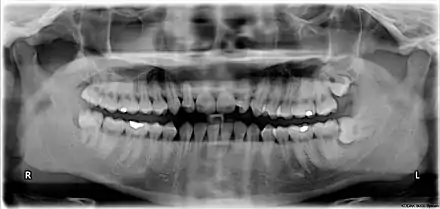

Orientation of the chart is traditionally "dentist's view", i.e. patient's right corresponds to notation chart left. The designations "left" and "right" on the chart below correspond to the patient's left and right.

ISO notation upper jaw

ISO notation lower jaw